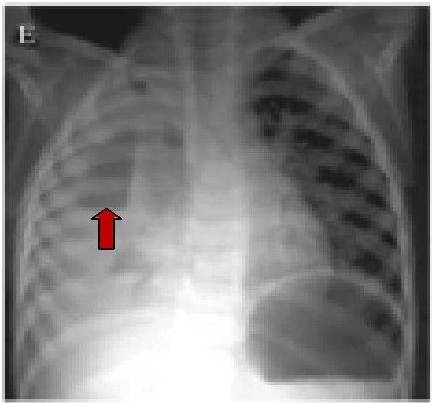

lancet插管后导致心包积气积液案例报道

可见到液平面及气胸.